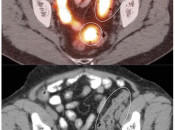

Hemorrhoidal Inflammation:

Focal intense uptake in the ano-rectal region is a very common finding. It is considered normal in the absence of an associated soft tissue abnormality. It is often attributed to hemorrhoidal inflammation.

Be careful to not confuse ano-rectal uptake (typically representing hemorrhoidal inflammation) with rectal uptake (often malignancy).